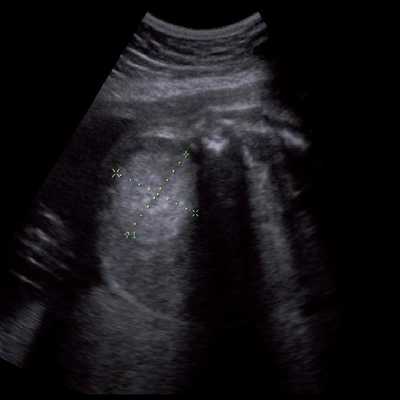

• Ультразвуковая диагностика. УЗИ во время беременности выявляет макроглоссию у плода еще в утробе матери. После рождения назначают ультразвуковое исследование щитовидной железы, чтобы исключить гипотиреоз. При наличии ощутимых образований в толще органа проводится УЗИ языка.

Под диафрагмой справа визуализировалось гиперэхогенное опухолевидное образование несколько неоднородной солидной структуры, с четкими ровными контурами, размером 50x38x35 мм. К нижнему полюсу данного образования прилежала правая почка, имеющая нормальные размеры, форму и структуру. Нижняя полая вена была смещена кпереди и влево. Обращала на себя внимание выраженная гепатомегалия, причем структура печени не была однородной. Она содержала множественные гиперэхогенные включения размерами до 17 мм, окруженные тонким гипоэхогенным периферическим ободком. Цветовое допплеровское картирование(ЦДК) демонстрировало интенсивную периферическую васкуляризацию опухоли (рис. 1-3).

Рис. 1. Нейробластома правого надпочечника плода. Беременность 31 нед 4 дня.